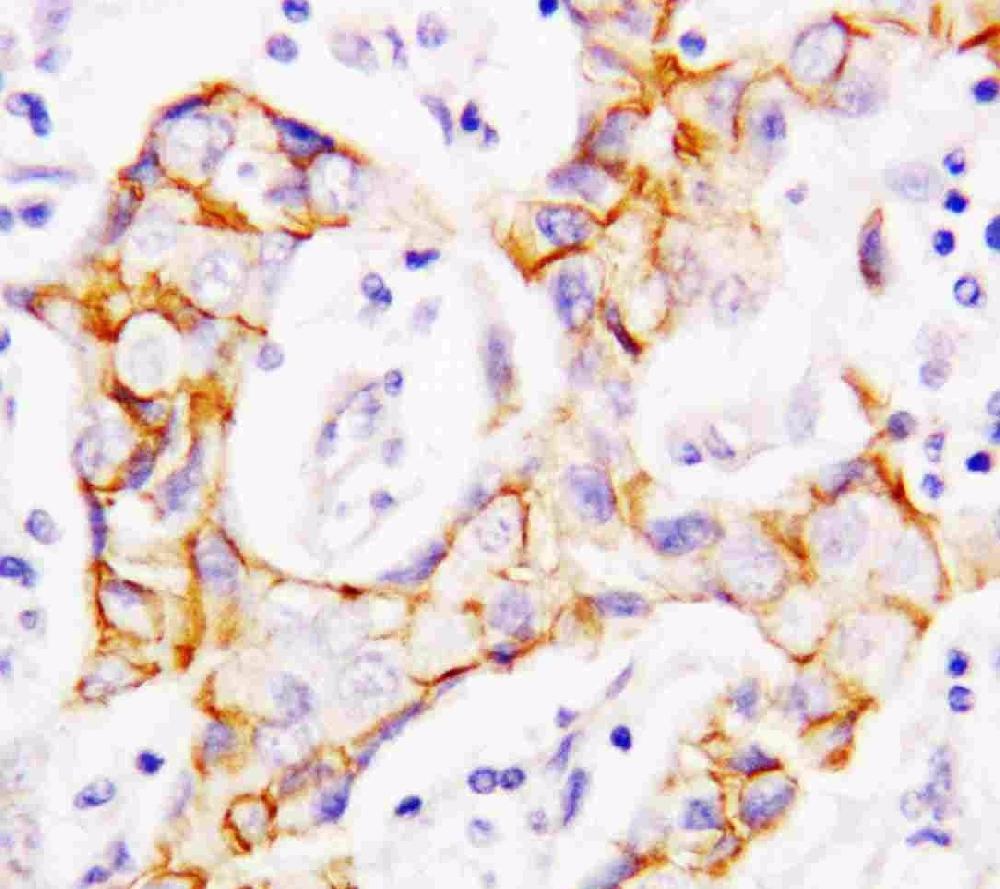

IHC analysis of Beta Catenin/CTNNB1 using anti-Beta Catenin/CTNNB1 antibody (PA1212).

Beta Catenin/CTNNB1 was detected in a paraffin-embedded section of human mammary cancer tissue. The tissue section was incubated with rabbit anti-Beta Catenin/CTNNB1 Antibody (PA1212) at a dilution of 1:200 and developed using HRP Conjugated Rabbit IgG Super Vision Assay Kit (Catalog # SV0002) with DAB (Catalog # AR1027) as the chromogen.